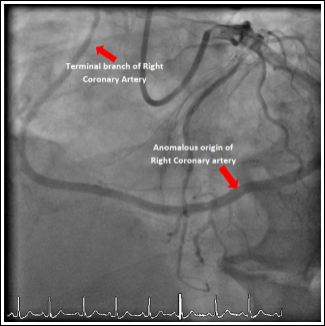

Our second case was a 67-year-old male with no prior cardiac history who presented with an acute anterior STEMI. Emergency coronary angiography revealed a single coronary artery with a critical stenosis in the proximal LAD (culprit lesion) and RCA arising from the distal circumflex artery (Figure 2). Successful primary PCI of proximal LAD was performed (Figures 3 & 4). Echocardiography was done during admission showing no associated structural heart disease. Patient was discharged after 4 days of hospital stay without any complications and remained asymptomatic during follow up.

Figure 2: Anomalous Origin of the Right Coronary Artery (RCA) from the Distal Circumflex Artery (LCx).